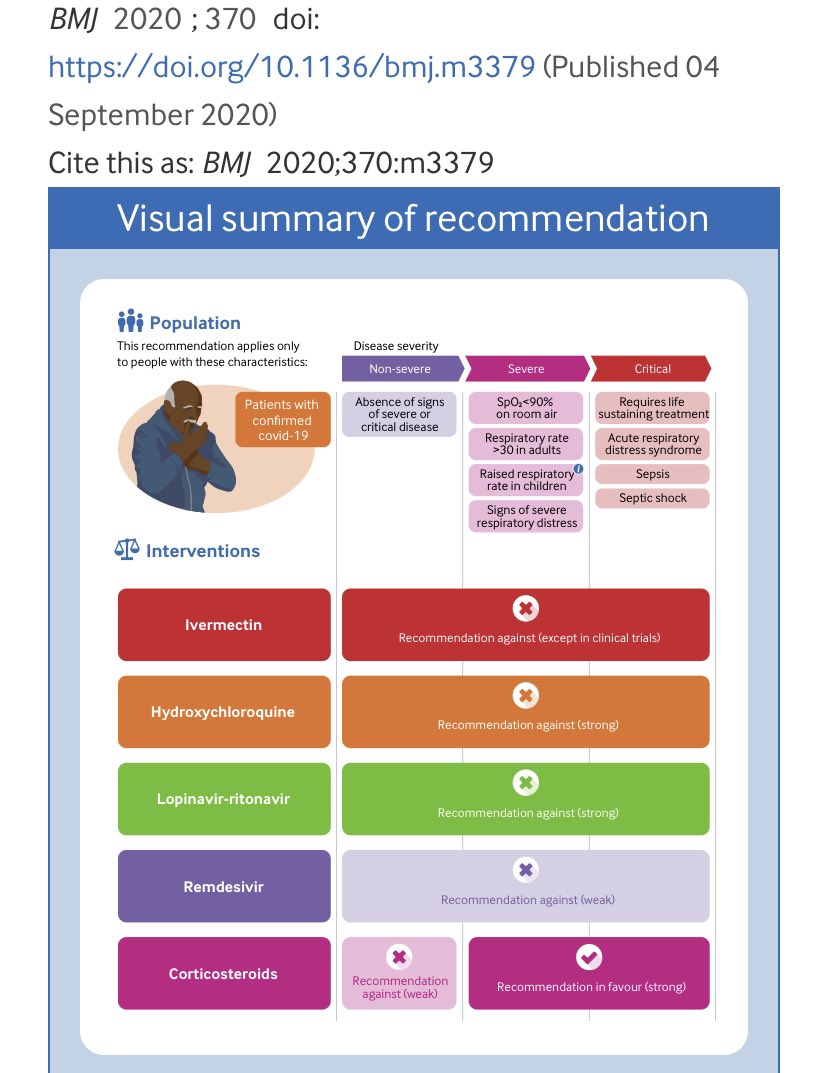

4/We really only have two good treatments for severe COVID-

1/ steroids and 2/ “proning”- which is flipping the patient lying on their back to lying on their front.

All of the other “wonder drugs” didn’t really pan out:

1/ steroids and 2/ “proning”- which is flipping the patient lying on their back to lying on their front.

All of the other “wonder drugs” didn’t really pan out: